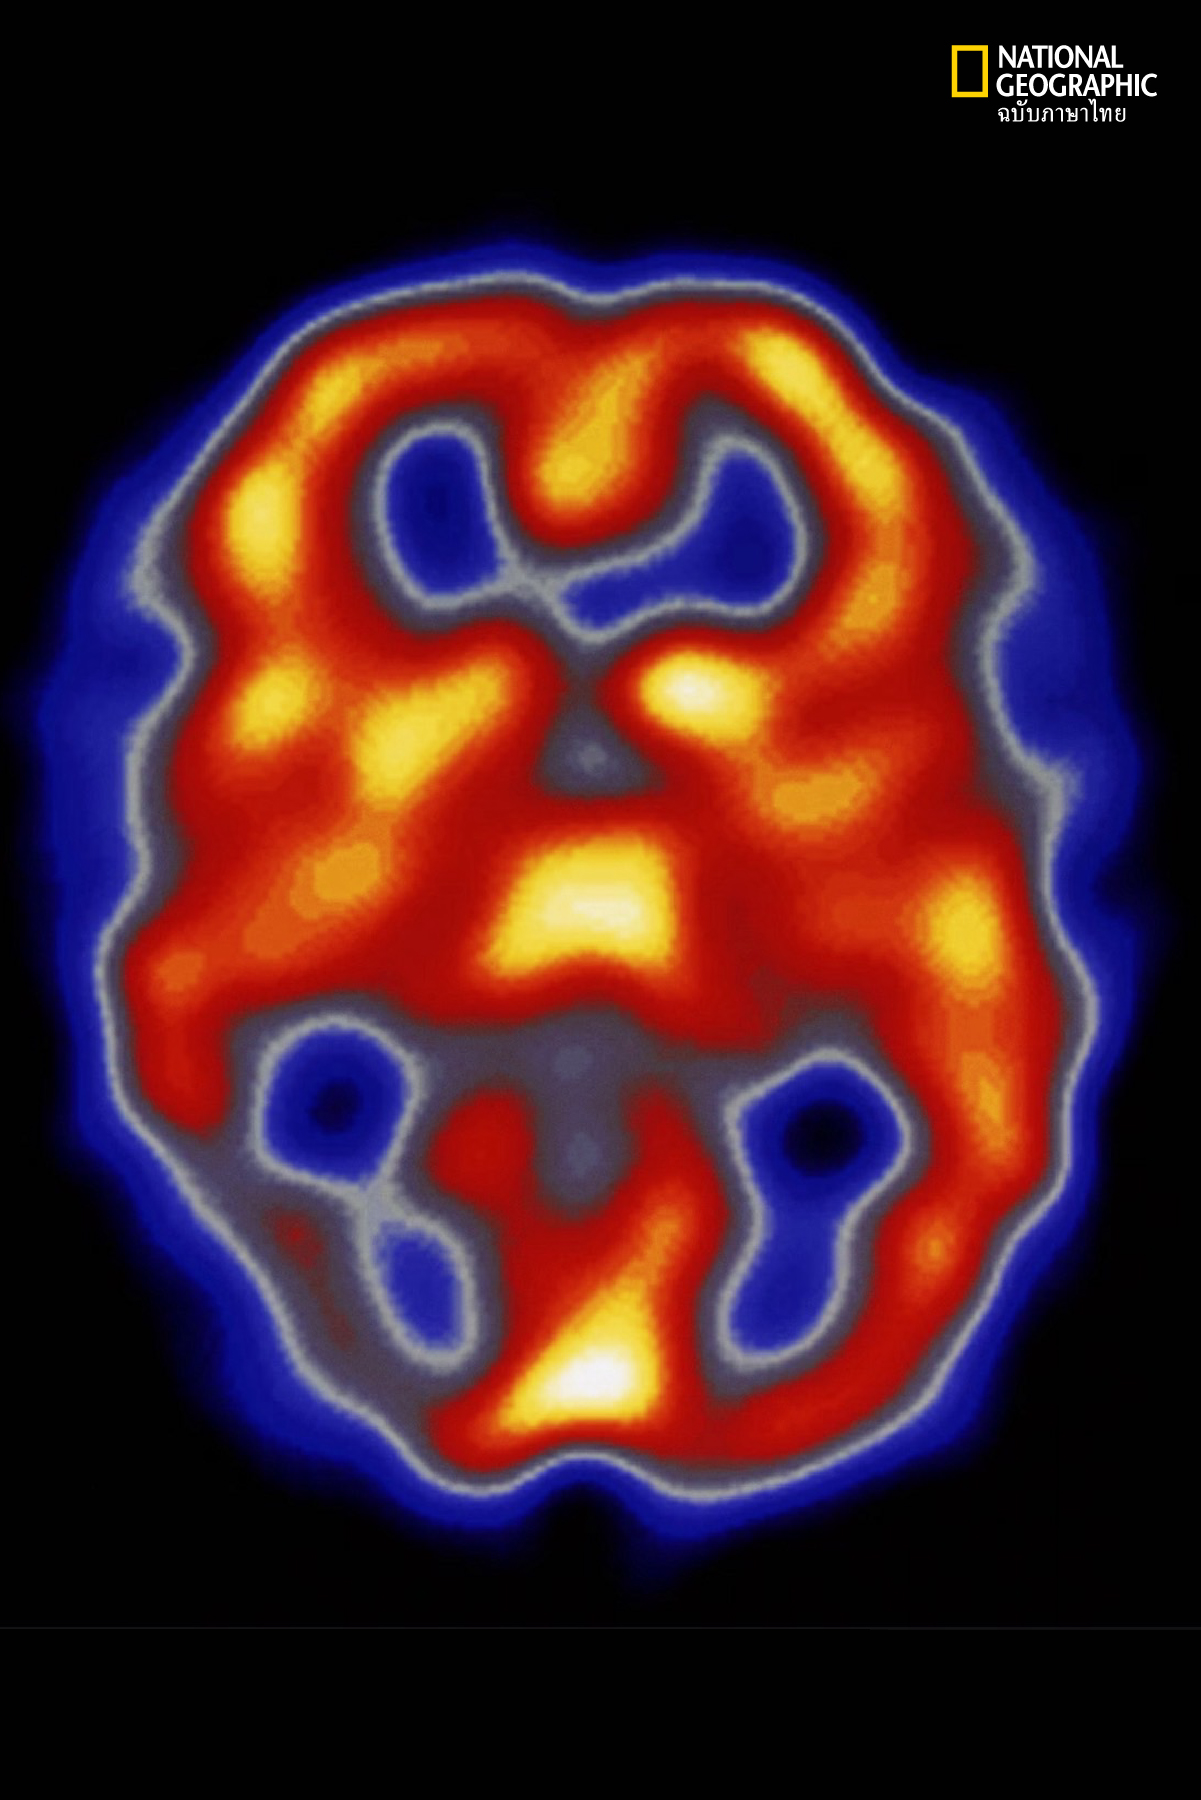

ความแตกต่างอย่างชัดของไมเกรนกับอาการปวดศีรษะประเภทอื่นนั่นคือ โรคไมเกรนจะมีลำดับแสดงอาการ 4 ระยะด้วยกัน ได้แก่ ระยะก่อนมีอาการ (prodrome phase) ระยะอาการเตือนนำ หรือออร่า (aura phase) ระยะปวดศีรษะ (headache phase) และระยะเข้าสู่อาการปกติ หรือระยะหลังมีอาการ (postdrrome phase)